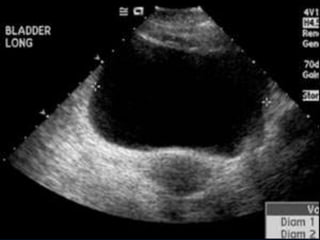

 UTI

 Abdomen (cholecystitis, pancreatitis, aortic

aneurysm, peptic ulcer disease, nephrolithiasis,

pelvic inflammatory disease, diverticulitis)